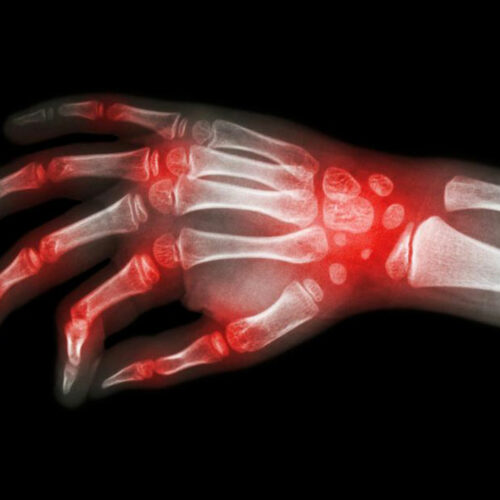

Lupus and rheumatoid arthritis are both autoimmune conditions that are often confused to be the same. The fact that these – rheumatoid arthritis, lupus are autoimmune diseases makes their symptoms similar too. Auto immune diseases are typically those conditions where the immune system of the body attacks healthy cells, causing inflammation, swelling, and pain in the affected areas.